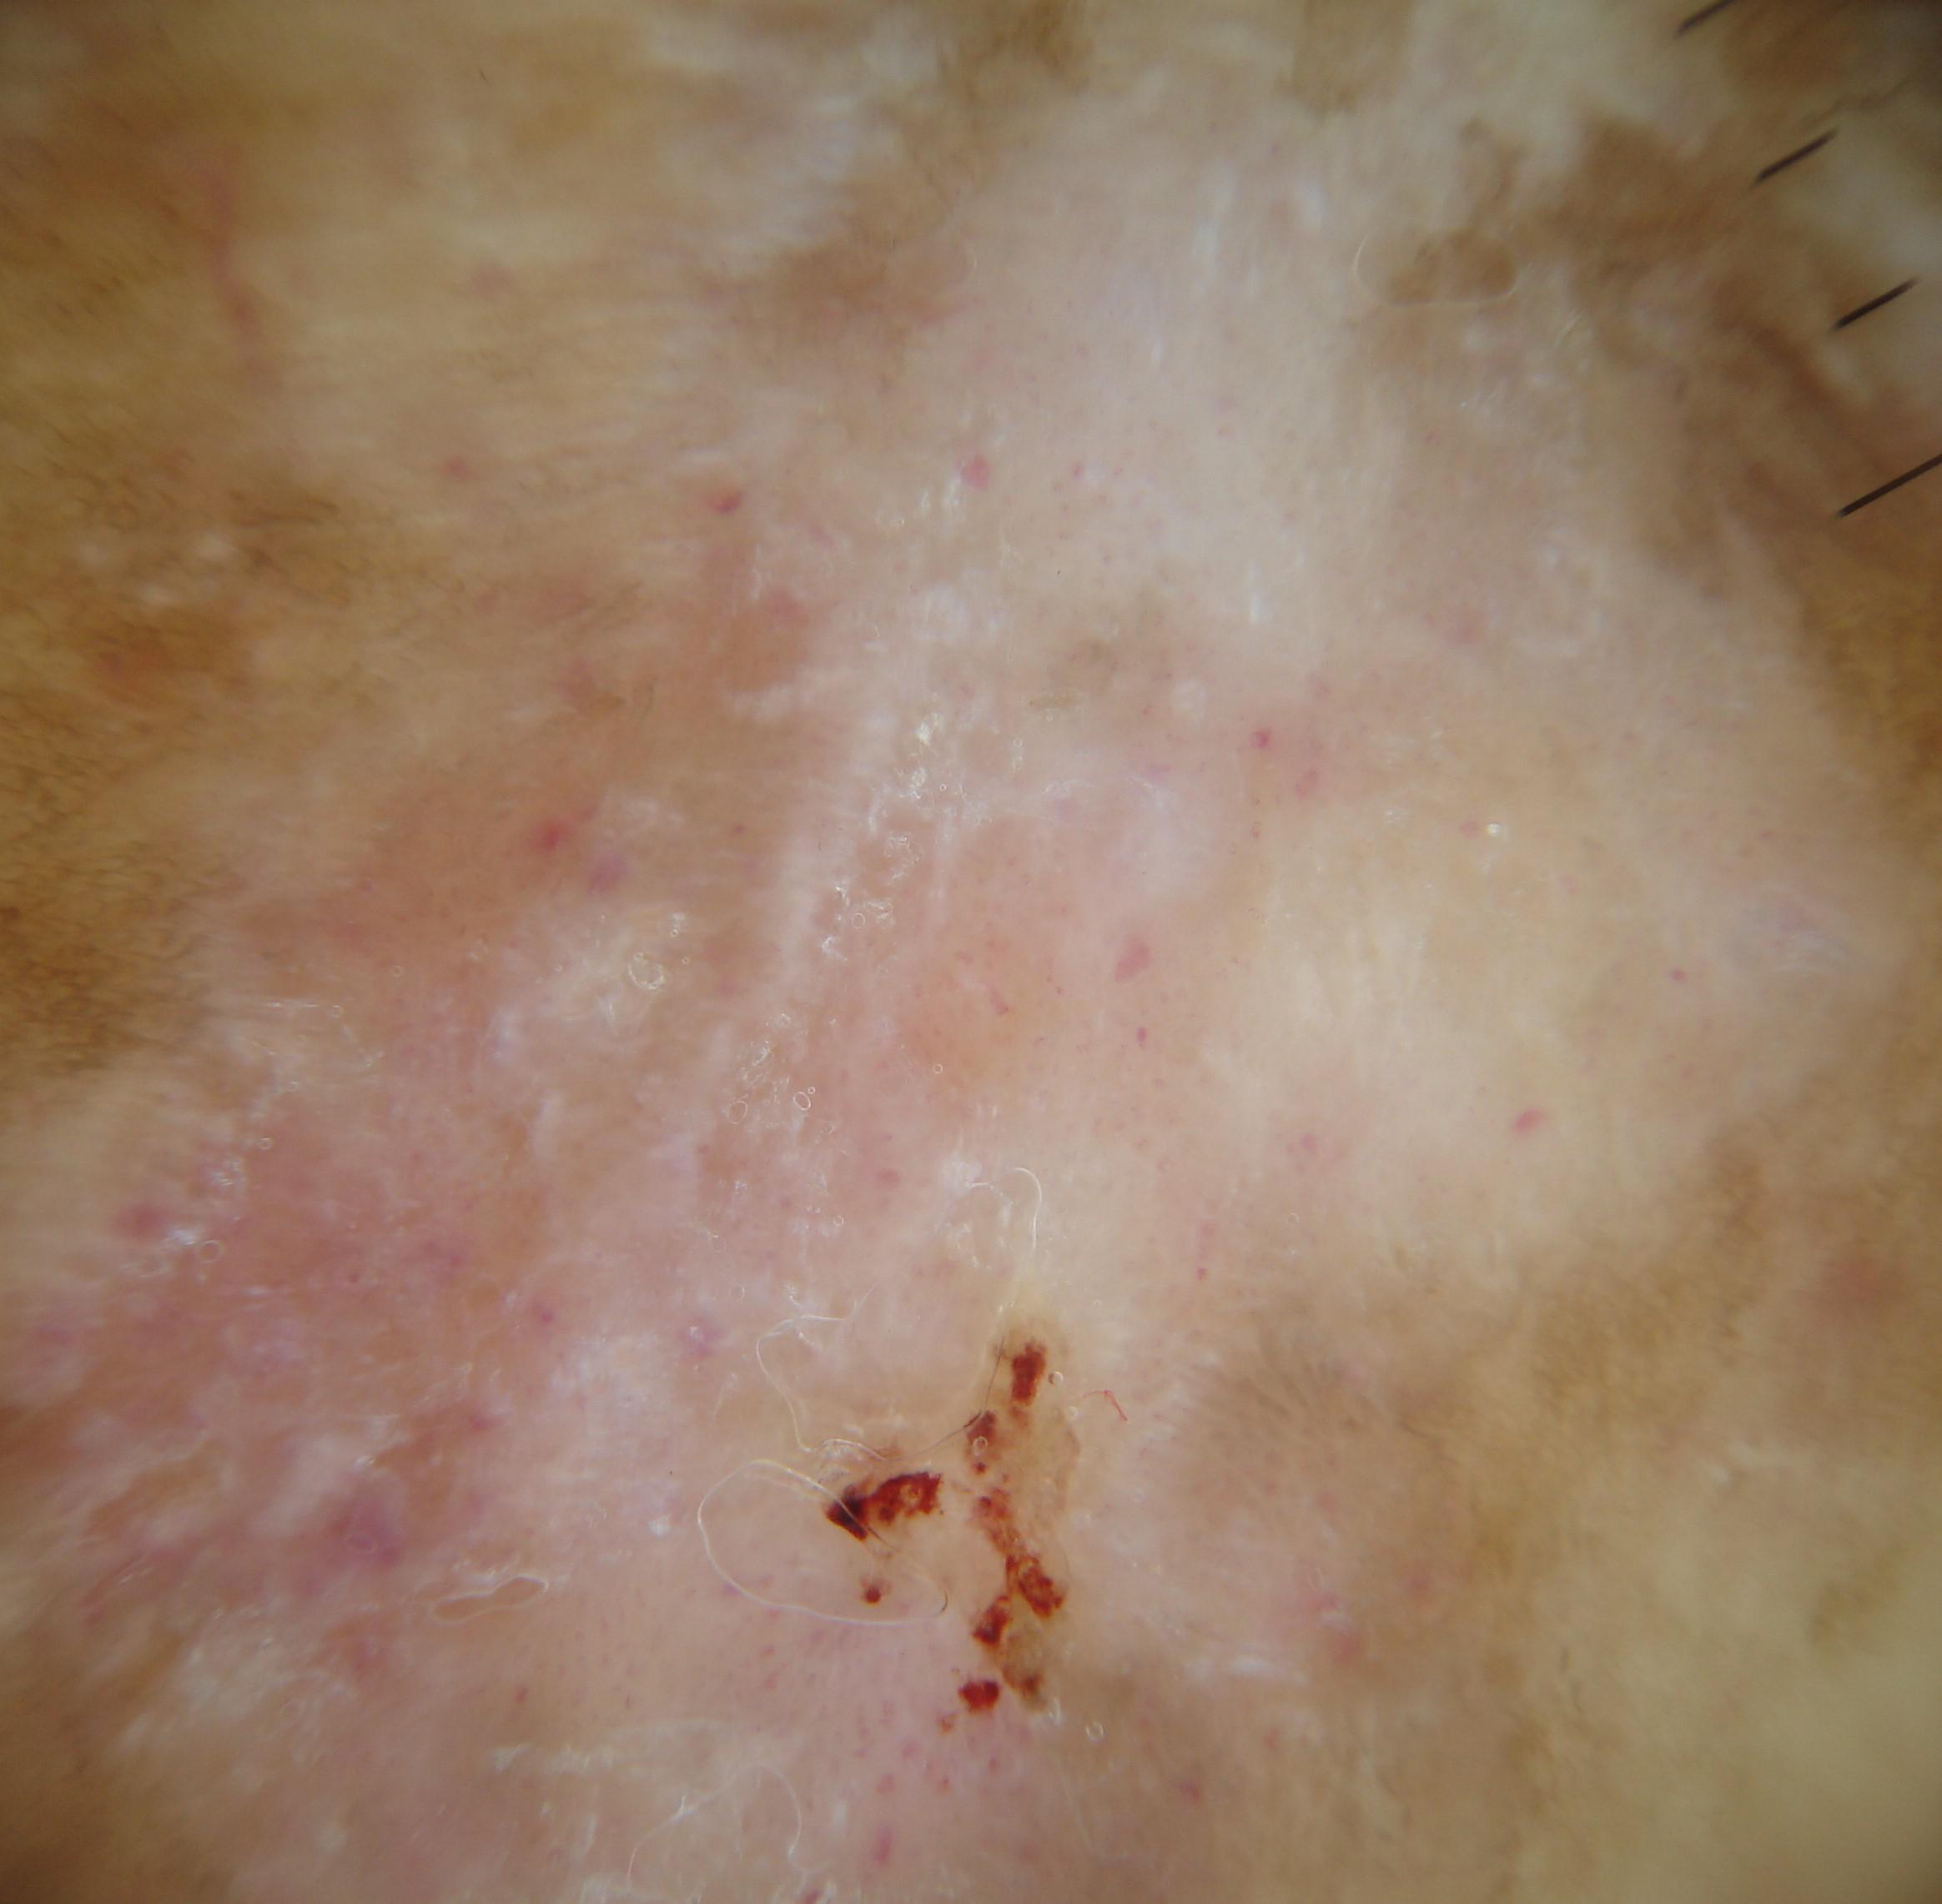

{

"age_approx": 75,

"anatom_site_general": "anterior torso",

"concomitant_biopsy": true,

"dermoscopic_type": "non-contact polarized",

"diagnosis_1": "Malignant",

"diagnosis_2": "Malignant melanocytic proliferations (Melanoma)",

"diagnosis_3": "Melanoma in situ",

"diagnosis_confirm_type": "histopathology",

"family_hx_mm": true,

"image_type": "dermoscopic",

"mel_thick_mm": "0.00",

"melanocytic": true,

"patient_id": "IP_1893317",

"personal_hx_mm": true,

"sex": "male"

}